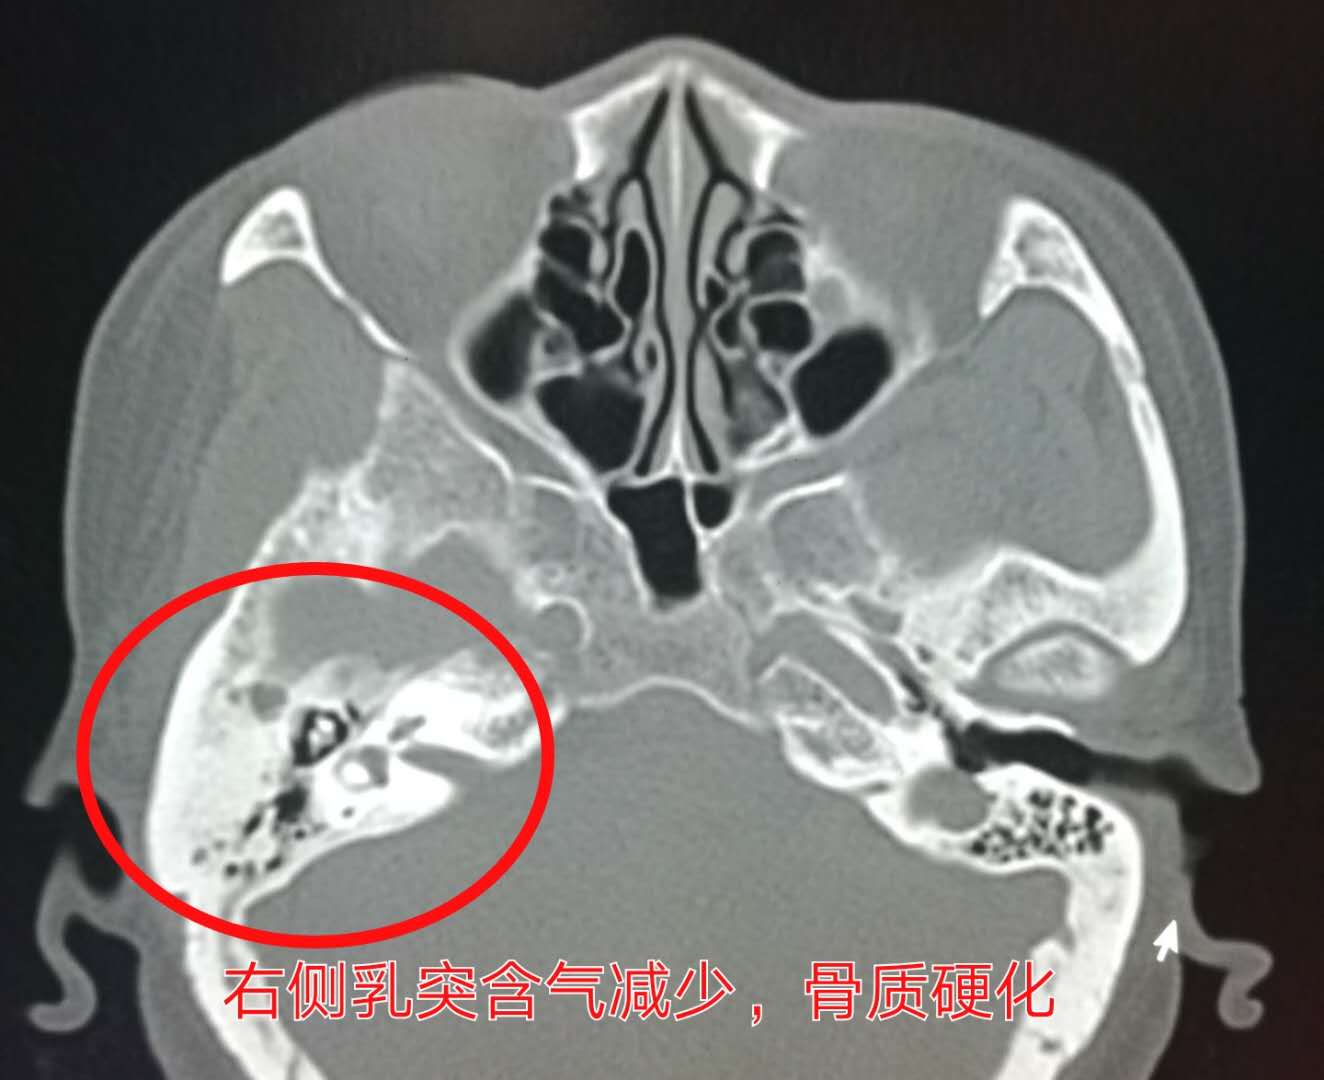

2.当发生中耳炎时,乳突小房气体减少,骨质硬化。

比如下图这个年轻姑娘,右耳听力下降两年——

对比上图可以看到,乳突气房密度增高,含气减少